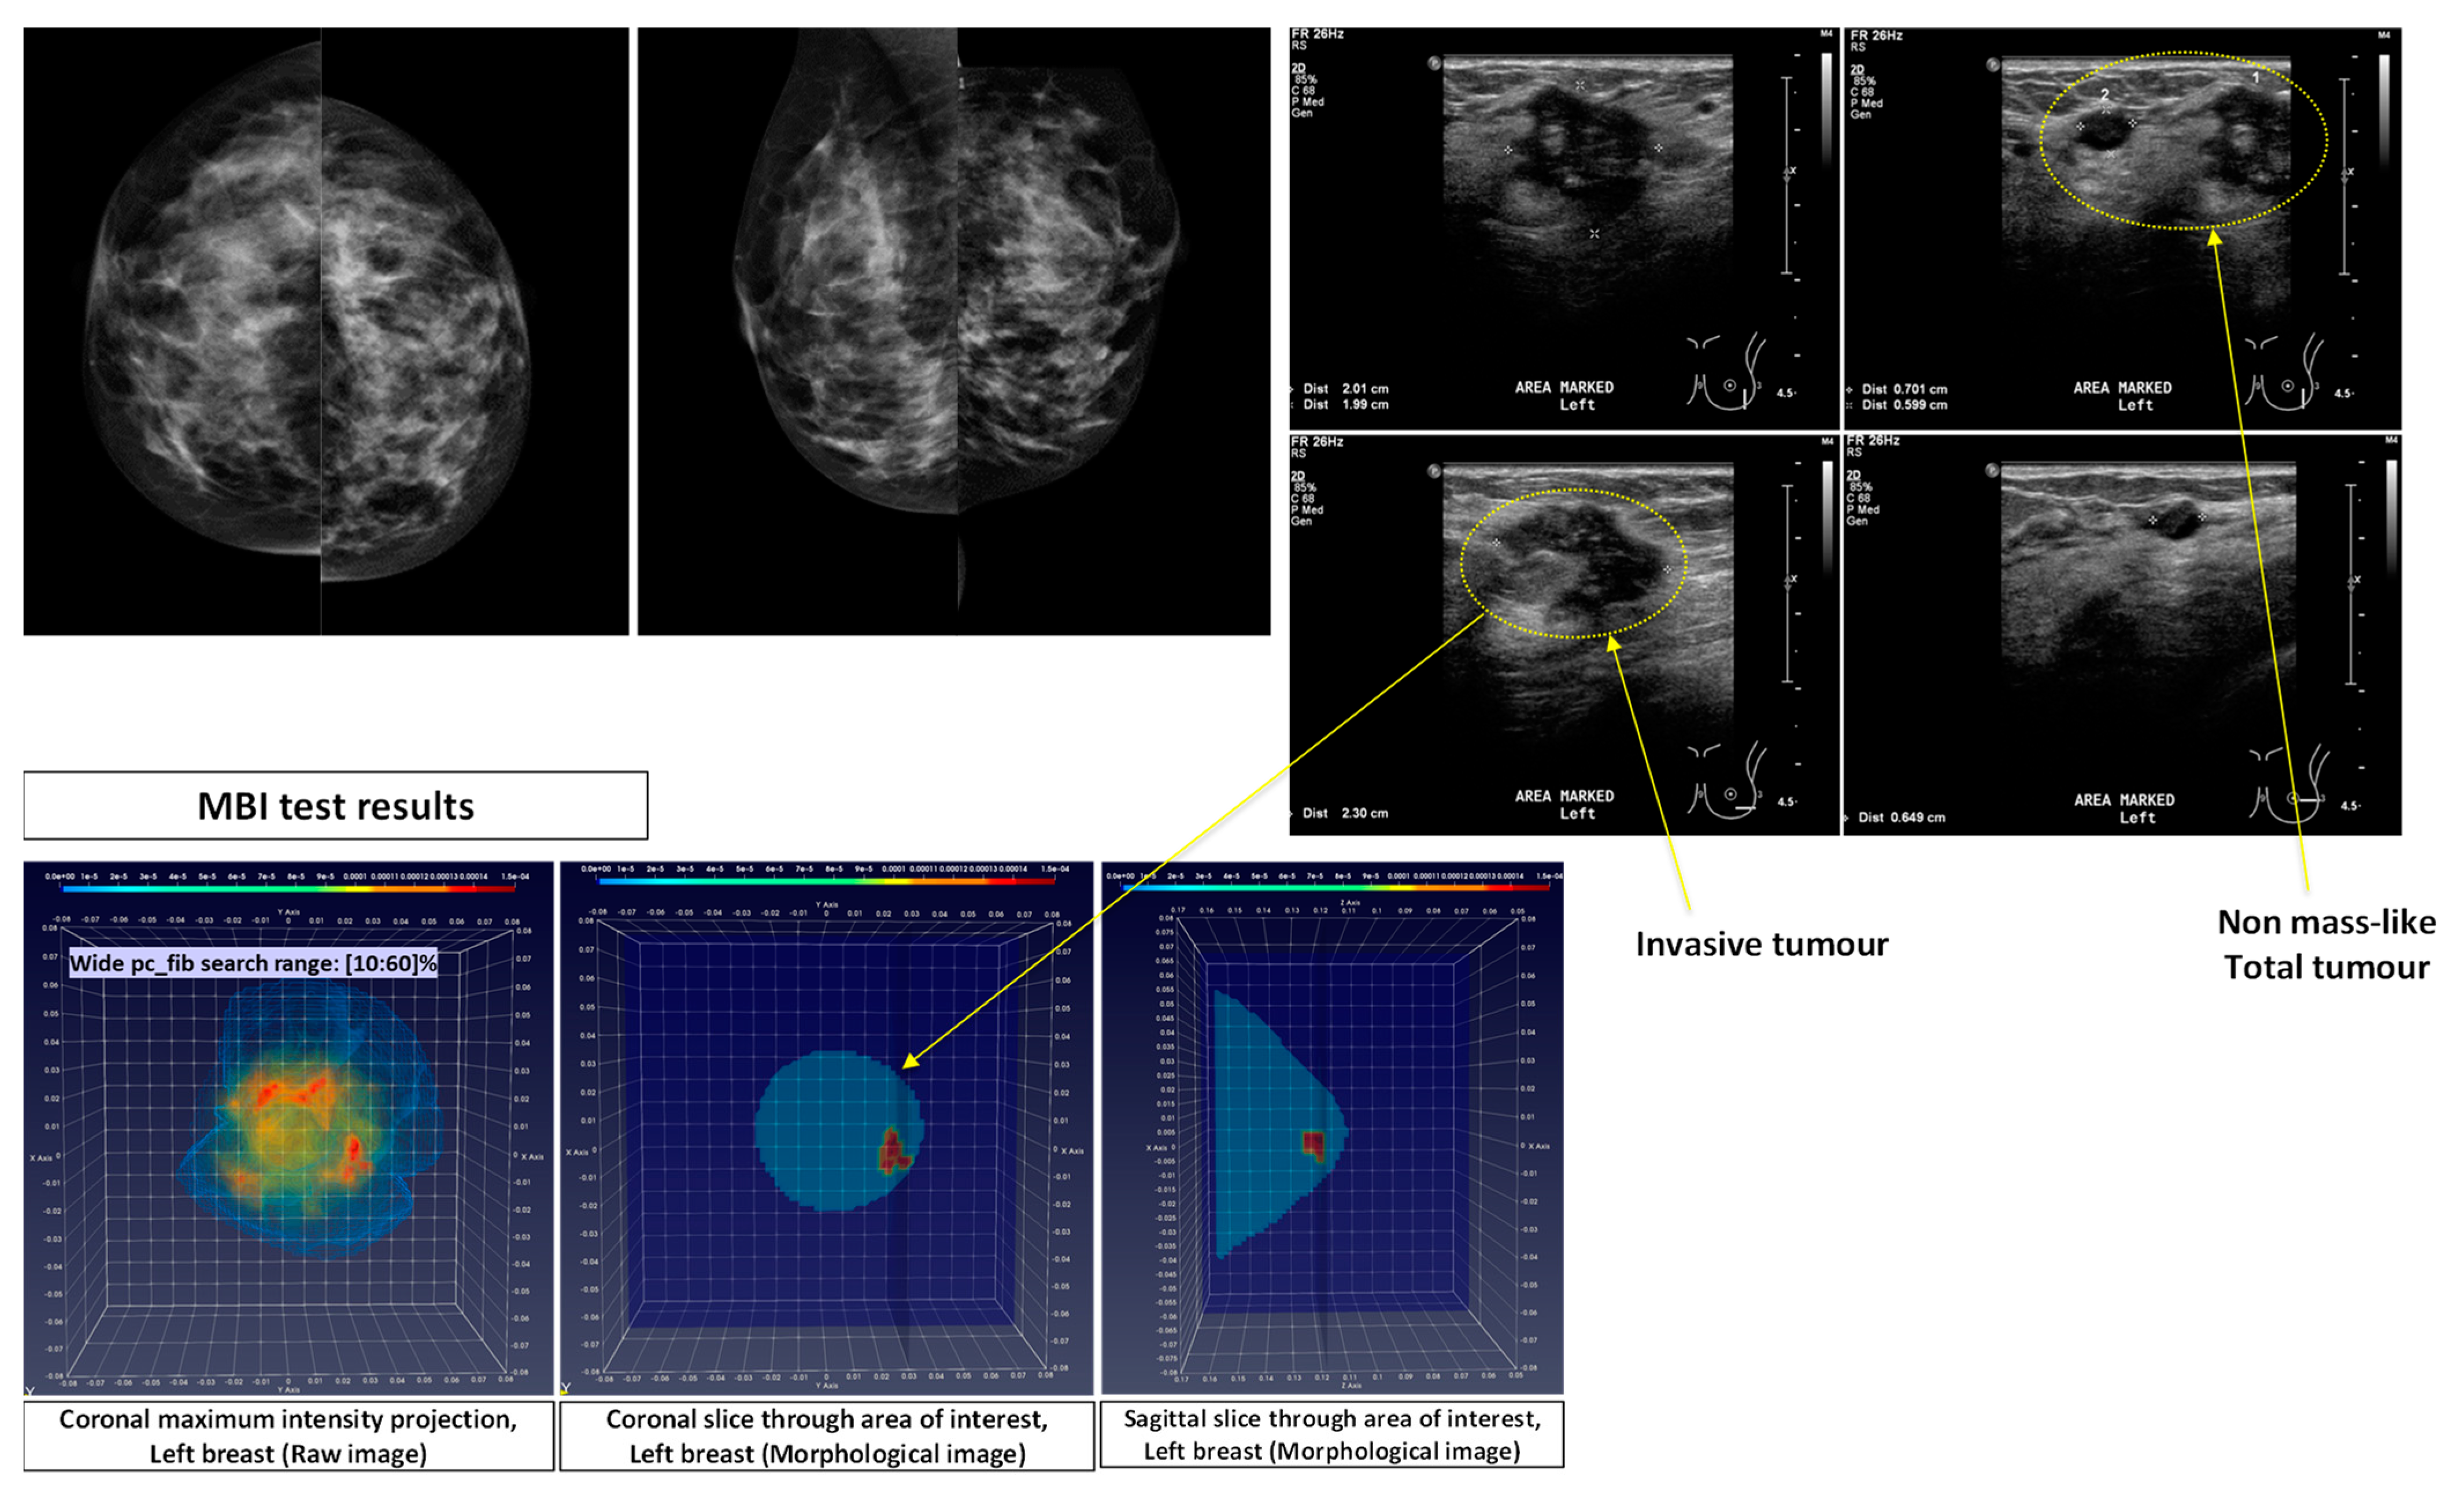

- Patient 032: Group-1: 54-years old patient with an Invasive Lobular Carcinoma (ILC) of size 30 mm (MRI data) at the 12 o’clock position of the Right Breast. Breast density: BIRADS Category c, Volumetric Breast Density (VBD) = 13.3%.

- pc_fib parameter setting in multiple search ranges: A large variability exists in the dielectric properties of each breast tissue type over the population, as demonstrated by multiple studies involving ex-vivo dielectric measurements of a large sample of excised breast tissues [18,19,20,21]. Considering that the full dielectric map of each breast cannot become practically available, data-driven techniques are employed in the Wavelia QIF to deduce the unknown dielectric properties of the healthy breast tissue in each breast, by assessing the pc_fib parameter. The pc_fib parameter, which is involved in the formulation of the illumination vector of the MBI sensor array, is physically associated with the percentage of fibro-glandular tissue along the propagation path within the breast, from a given transmitting antenna to the interrogated imaging pixel and back to a given receiving antenna, as defined in Equations (1)–(3). The Wavelia QIF generates a set of parametric MBI radar images under various assumptions on pc_fib. The generated set of parametric images is further evaluated in terms of focusing, using the image curvature [22,23] as a focusing quality measure. To better handle the heterogeneity of the breast and potentially better reveal the non-uniform angular response of the breast lesions to MBI, the pc_fib parameter setting is performed independently in each azimuthal imaging sector, while employing multiple search ranges. In the Wavelia QIF, X1 wide and X2 narrow pc_fib parameter search ranges are systematically employed for image formation, thus a total number of X = (X1 + X2) MBI images are formed per patient’s breast.

- Wide pc_fib search range #1 (W1): pc_fib ϵ [10 20 30 40 50 60]%

- Wide pc_fib search range #2 (W2): pc_fib ϵ [20 30 40 50]%